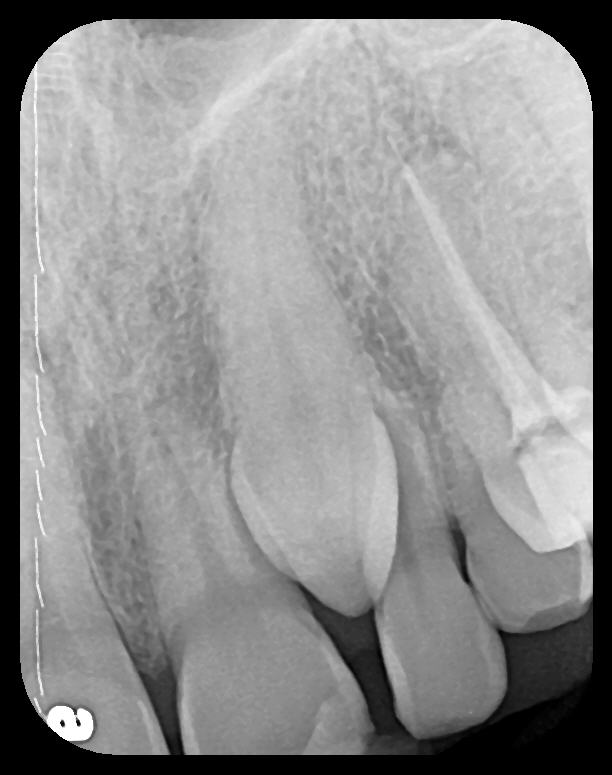

As displayed here, the 2D radiographic images in Figure 3 through Figure 8 can alert the clinician to the need for a further 3D CBCT analysis to properly ascertain the anatomy and extent of the pathology that is initially visible in the intraoral radiographs. Proper treatment or referral to the appropriate specialty practice can follow.5,6 No. 2 PSP radiographs, when used in a conventional full-mouth series of radiographs on a patient with a relatively complete dentition, will routinely allow visualization of the anatomy of third molars, mandibular canal, maxillary sinuses, full dental root morphology, and bone anatomy beyond the apices2,16,17 (Figure 9 and Figure 10).

Fig 10.

A hemostat was used to obtain this PSP PA image of a potential fixed

prosthesis abutment, tooth No. 32. The hemostat is visible in the upper

left corner of the image. Hemostat stabilization of an HW sensor is

not possible and can damage the sensor if attempted.

Figure 10